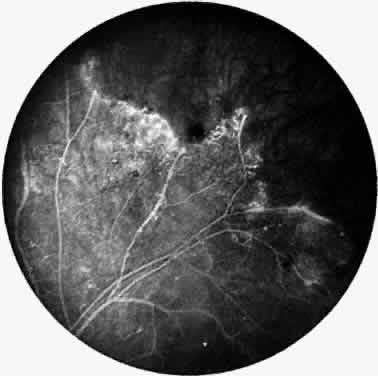

Signs of ocular inflammation are commonly encountered in Eales' disease, especially early in its course. Vascular sheathing is seen in most patients (Fig. 1). The degree of sheathing ranges from thin white lines on both sides of the blood column to thick heavy exudative sheathing. Areas of sheathing frequently leak dye with fluorescein angiography (Fig. 2). However, there is not a direct correlation between the regions of sheathing and staining.

Fig. 2. Fluorescein angiogram demonstrating abnormal vascular staining in a patient with Eales' disease. There was venous sheathing in these areas.

A varying degree of peripheral retinal nonperfusion is present in all patients with this disease. The nonperfusion generally is confluent and sharply demarcated from the posterior perfused retina (Fig. 3). Fine white lines representing the remains of obliterated large vessels (ghost vessels) often are seen in the area of nonperfusion. The temporal retina is most commonly affected.

Fig. 3. Fluorescein angiogram of the peripheral retina demonstrates the junction of normally perfused retinal vessels adjacent to an area of nonperfused retina. Notice the vascular abnormalities at the junction.

Elliot and Spitnas and colleagues have documented the abnormalities at the junction between the anteroperipheral nonperfused and the posterior perfused retina.9,10 Intraretinal hemorrhages often first appear in the affected area, followed by an increase in vascular tortuosity with frequent collateral formation around occluded vessels (see Fig. 3). Microaneurysms, arteriovenous shunts, and venous beading are commonly seen at the junction (Fig. 4). Fluorescein angiography enhances these abnormalities and often demonstrates staining at the stumps of obliterated vessels.